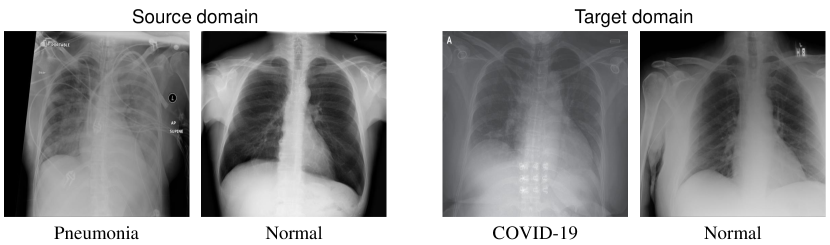

Other than benchmarking L2M on popular public datasets including Office-31, Office-Home, ImageCLEF-DA, and VisDA-17, we compare the performance of several DA methods including L2M in a real application. Different from public datasets, this application will prove the effectiveness of L2M and other DA methods in a real-world task, which is more appealing and inspiring.

We present more details for applying L2M to COVID-19 chest X-ray image adaptation tasks. COVID-19 is a specific type of pneumonia compared to the normal kind of pneumonia, and there is not too much COVID-19 data available, it becomes necessary and feasible to use the sufficient labeled pneumonia data to help classify the COVID-19 symptom. Therefore, this task is a binary classification task, where the source domain is the well-labeled pneumonia data to classify whether this patient is having pneumonia or not, and the target domain is the unlabeled COVID-19 data. Out task is to classify whether each of the the target domain samples is having a COVID-19 symptom or not.

This is a binary classification task, i.e., the normal category vs. pneumonia on the source domain, and the normal category vs. COVID-19 on the target domain. We also notice that this dataset is highly-imbalanced (as shown in the next section). Therefore, for better illustrate the results, we adopt F1 score, Recall, and Precision as the evaluation metrics rather than classification accuracy. These metrics are better for imbalanced classification tasks. It also demonstrates our contribution that L2M can achieve robust preformance in imbalanced tasks compared to other DA methods.

C.1 Dataset

Table 6 shows the description of the dataset111The dataset is available at https://github.com/qiuzhen8484/COVID-DA. Note that in this task, we use some COVID-19 data as the validation set to better tune the hyperparameters. In the source domain, there are two classes: normal and pneumonia, while there are normal and COVID-19 classes in the target and validation dataset. Fig. 3 shows some examples from the source and target domain. It is clear that data from two domains are very similar especially for pneumonia and COVID-19 classes. Therefore, it is feasible to perform domain adaptation or transfer learning between these two domains.

Refer to caption

Figure 3: Samples from the source and target domain.